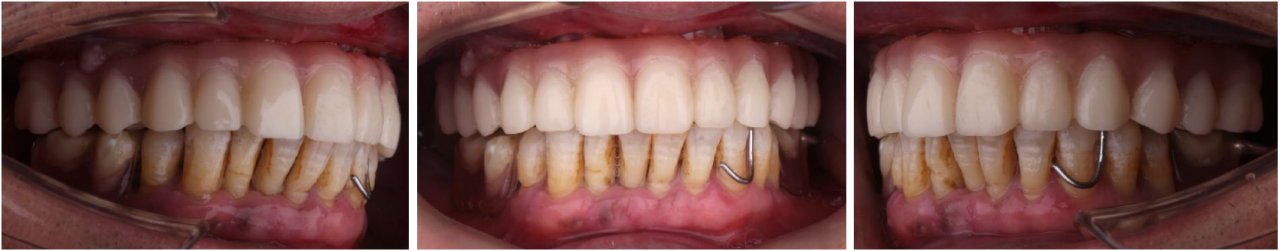

即刻修复3个月后:

上颌边缘骨稳定,行下颌后牙区种植,下颌植入4颗中科安齿种植体

即刻修复5个月后:

边缘骨稳定,上下颌同期行永久修复